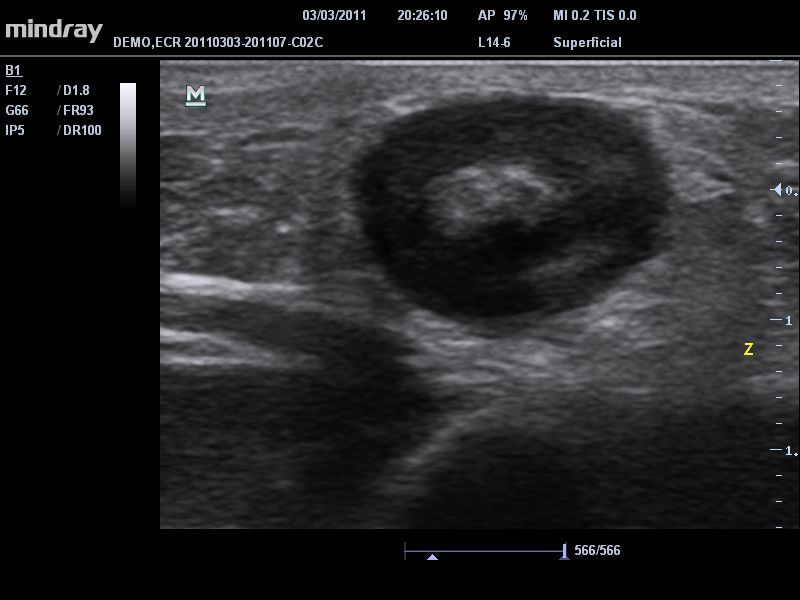

Ультразвуковая система Mindray DC-T6 – это инновационный аппарат для проведения высокого уровня диагностики с качественной визуализацией и широким спектром применения. Платформа рекомендована для использования в коммерчески многопрофильных медицинских учреждениях и государственных лечебных клиниках.

Система сочетает в удобном и компактном корпусе не только традиционные возможности современного УЗИ-сканера, но и инновационные технологии, повышающие точности диагностики состояния пациентов.

• Режимы сканирования: B/M/CFM/PDI/Направленный PDI/PW, HPRF, Тканевая гармоника, М- и цветной М-режим.

• iClear™: технология подавления зернистости увеличивает контрастное разрешение поврежденных участков без ущерба для пространственного разрешения.

• iBeam™: позволяет более точно определять границы благодаря объединению нескольких изображений, полученных под разными углами, в одно изображение в режиме реального времени.